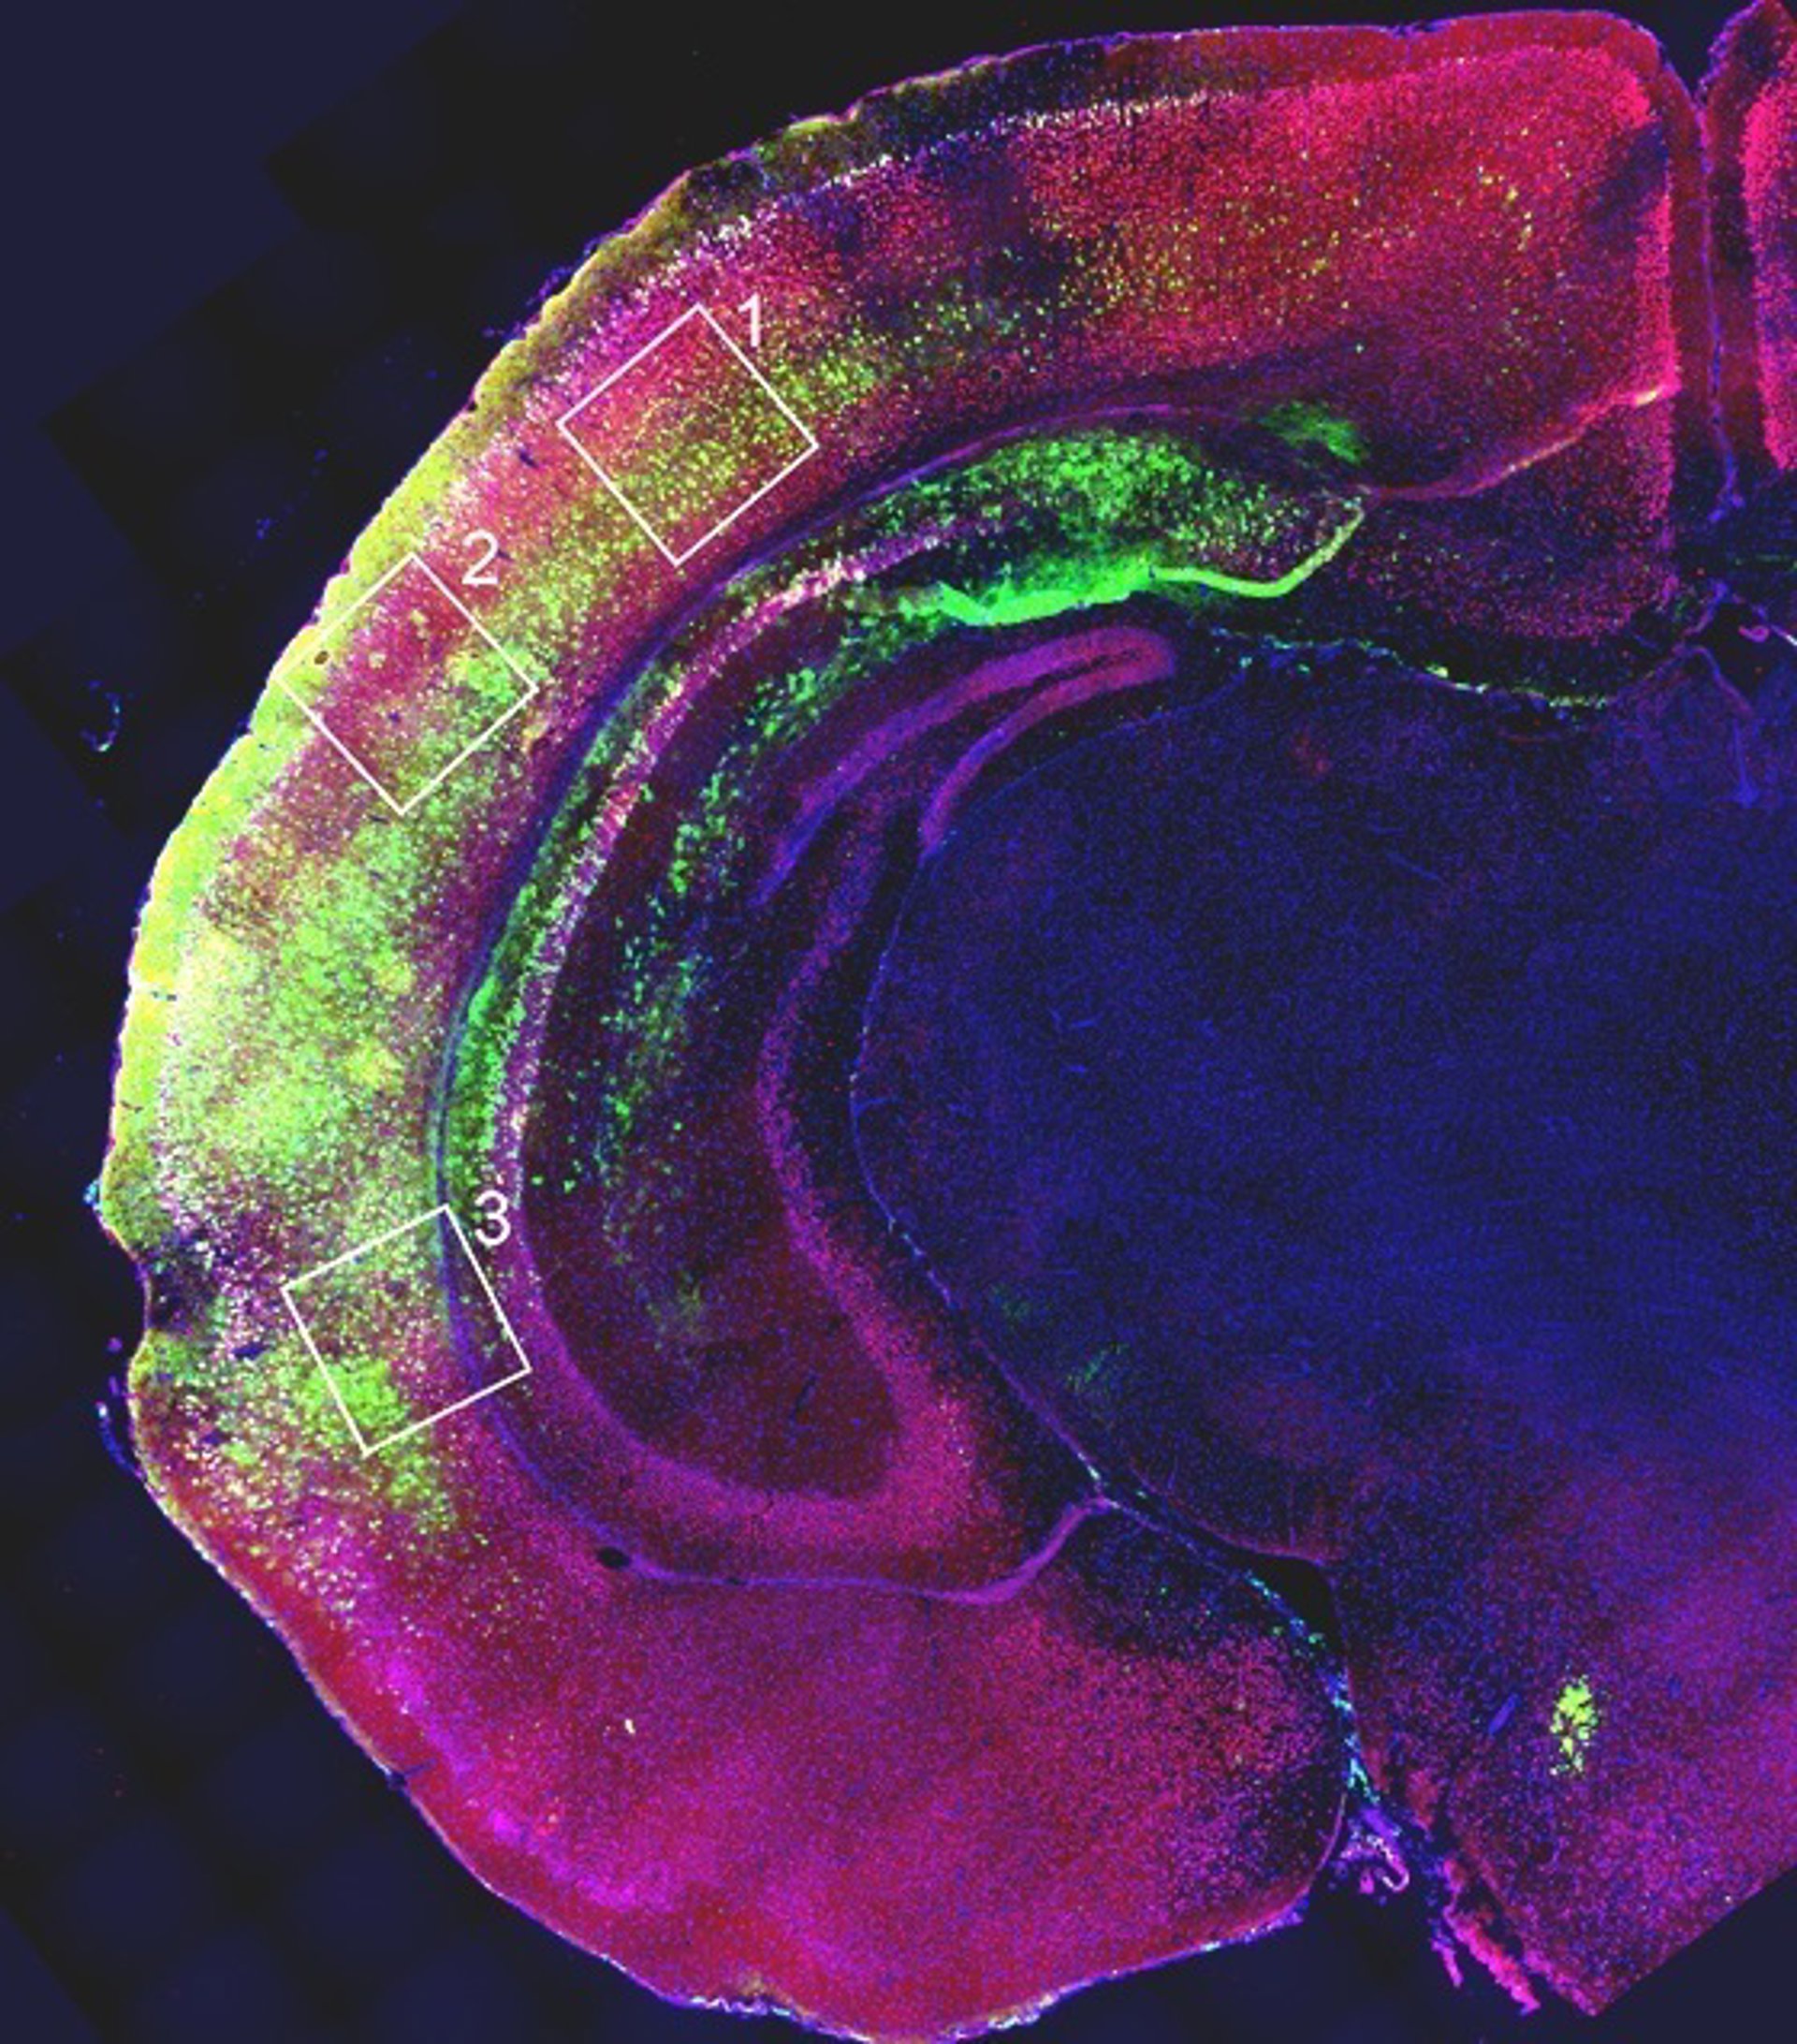

El equipo realizó varias pruebas. En primer lugar, in vitro, los científicos verificaron si la estimulación a través del ARN promotor era capaz de amplificar la actividad del gen sólo donde se necesitaba. "FOXG1 sólo está activo en el cerebro anterior y no queremos de ninguna manera que actúe en otra parte del sistema nervioso o el cuerpo", explica Mallamaci.

"Las pruebas dieron resultados positivos: después de la estimulación, el gen siguió expresándose sólo en las células donde previamente había estado activo y se mantuvo en silencio en los tejidos donde normalmente no funciona. Es muy importante que la actividad observada aumentó por un factor no muy lejos de 2, es decir, esa 'doble' expresión que estábamos tratando de lograr", subraya.

El tercer paso fue ver si la estimulación también funcionaba in vivo. "La prueba se realizó en ratones sanos y encontramos que la estimulación era aún más eficaz in vivo que in vitro", concluye Mallamaci. "Todavía estamos al principio de un proceso clínico muy largo que podría llevar algún día al tratamiento -matiza--. Sin embargo, los resultados son muy claros y definitivamente nos animan a continuar esta línea de investigación. Los próximos pasos serán pruebas in vivo en modelos animales afectados por la enfermedad".